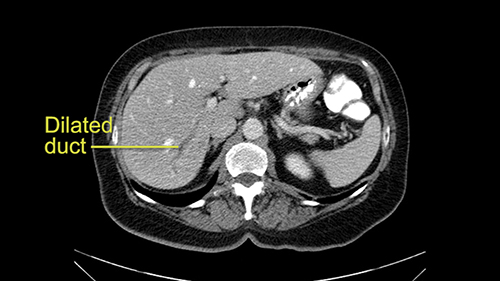

Intrahepatic ductal dilatation in Sg 7

The third issue for this patient is that in Segment 7, I notice that there is intrahepatic ductal dilatation due to a small tumor causing obstruction. Now this tumor is not well-visualized on the most recent CT scan but I want to carefully evaluate the bile duct, where the obstruction is, so at the time of surgery I can be sure to remove the affected bile duct as well as the small tumor that is causing the ductal dilatation.

So in light of the CT findings, the plan for this patient is a right hemihepatectomy that would encompass all the small tumors including the one in 4a-8, 5, 6-7; and the reason that I would do a full right hemihepatectomy is because of the intraductal dilatation in Segment 7 that makes me suspicious that there is a tumor that cannot be removed with simple wedge resections.

My name is Steven Gallinger, I’m a professor of surgery at the University of Toronto and an HPB surgeon at the University Health Network. I’ve been asked to comment on this case and discuss preoperative planning, potential slowing down moments. It’s an interesting 65-year old woman with right sided colon cancer and synchronous liver metastases: small metastases in the right lobe of the liver and she had the primary tumor resected and then underwent neoadjuvant chemotherapy for her small liver metastases in Segments 4, 5, 6 and 7. The distribution of the metastases is interesting. They are small lesions, but the interesting additional feature is isolated segmental dilatation of the Segment 7 bile duct which suggests an intrabiliary metastasis somewhere near the origin of the main Segment 7 duct. Because I can trace it close to the porta [hepatis], I would assume that it’s pretty close to the bifurcation of the main right sided bile ducts but I can’t actually see the actual tumor. It’s really just presumptive.

She underwent neo-adjuvant chemotherapy and then had a series of additional investigations and the one that I’m focusing on in more finer detail is an MRI with Primovist and I’ve had the benefit of looking at the report. The main issues are in Segments 5,6, and 7. Three small metastases that remain and the radiologist also comments on the lack of biliary dilatation which was present before; implying that the intrabiliary metastasis somewhere at the origin of the Segment 7 duct, has regressed or been adequately well treated with chemotherapy. That’s probably where the difficult decision making comes in the OR. So from an oncologic point of view, I would plan for a right hepatic lobectomy. The rationale would be that this would include the more peripheral Segment 5, 6, 7 metastases that are obvious but also would take care of the presumed Segment 7 intrabiliary metastasis that does not actually visualize on any of the scans but is assumed to be there with evidence of the duct dilatation which then resolved. One could argue whether we should preserve liver and ignore that duct dilatation that was there before but I think my own preference would be to resect the right lobe and that would certainly include any residual disease in that Segment 7 bile duct and moreover, coming back to do a completion right hepatic lobectomy would be difficult particularly around the porta where this metastasis is presumably still there and even if its quite small.

I am Professor Jacques Belghiti, hepatobiliary surgeon. I practiced at Beaujon Hospital at Paris Diderot University Paris 7. I will discuss the case of a 65-year old patient who has hepatic metastases from a colon cancer operated on one year before. Two particular points with this patient: She has had a cholecystectomy at the time of colectomy, and at the discovery of the lesions in which there were 3, all located in the right liver, we noted the existence of biliary dilatation. This biliary tract dilatation could have been a consequence of the cholecystectomy, or due to a particular form of metastasis with biliary infiltration; and my impression is that the second hypothesis should be supported for two reasons. The first reason is that on the initial CT scan, we had a feeling that the biliary tract dilatation was associated with a small tumor/lesion. The second reason is that the dilatation decreased after several courses of chemotherapy. I don’t know how many courses of chemotherapy she had, but in any case, there exists some lesions of the hepatic parenchyma, with steatosis that may have been a consequence of this chemotherapy. After several courses of chemotherapy, we see at least 2 lesions persisting in the posterior sector of the right liver and dilatation of the biliary tracts. There might be another lesion at the junction of Sg 5 and 8. So this patient should now be operated on since we are faced with lesions that persisted after chemotherapy.